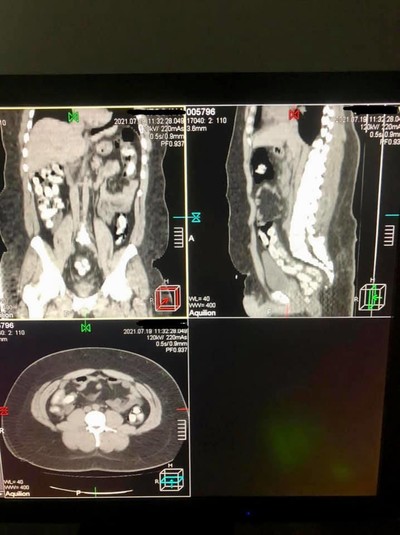

Багатоетапна спецоперація із виявлення зловмисників завершилася у Міжнародному аеропорту «Бориспіль» затриманням двох наркокур’єрів із черговими партіями кокаїну. Один із них приховав «товар» в особистих речах. Інший намагався перевезти через держкордон понад 1 кг кокаїну у кишково-шлунковому тракті. Загалом у ході слідчих дій правоохоронці виявили у наркокур’єрів партію кокаїну загальною вагою 2 кг.